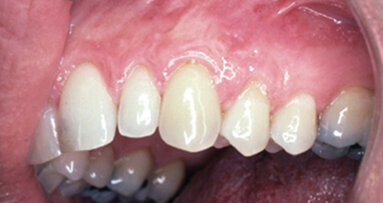

This case describes two areas of recession in a single mouth, thus influenced by identical saliva and oral habits. I used the same cosmetic surgery technique on both areas but used a barrier on only one of the areas (Figs. 3–6).

The 10-plus year outcome (Fig. 7) shows complete root coverage of gingiva on tooth #11, where the barrier collagen TranZgraft was used. The adjacent bicuspid #12 had the same coronal repositioned gingival flap procedure at the same time but without use of the connective tissue barrier.

The results clinically demonstrate that use of a barrier helped achieve complete restoration of gingiva tissue on previously recessed root. The same technique in this case, without the use of a barrier membrane, results in no root coverage (Fig. 7).

This particular case would appear to confirm that barriers aid in predictability of root coverage when using this cosmetic surgery technique.